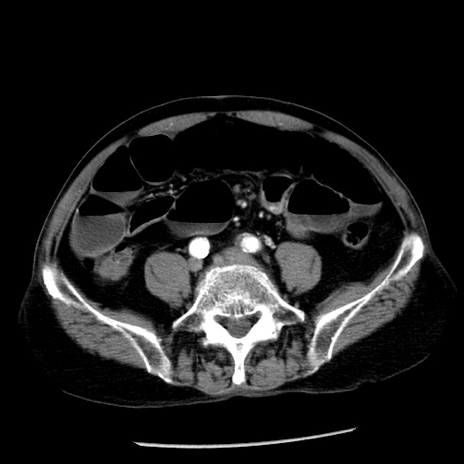

症例26(横断像)

【症例】80歳代男性

【主訴】嘔吐

【現病歴】昨晩2回嘔吐あり、今朝になっても嘔吐あり。来院。

【既往歴】胃潰瘍

【身体所見】意識清明、BT 37.6℃、BP 166/95mmHg、HR 100bpm、SpO2 97%、腹部:平坦・軟、腸蠕動音聴取良好、圧痛なし。

【データ】WBC 21900、CRP 1.46